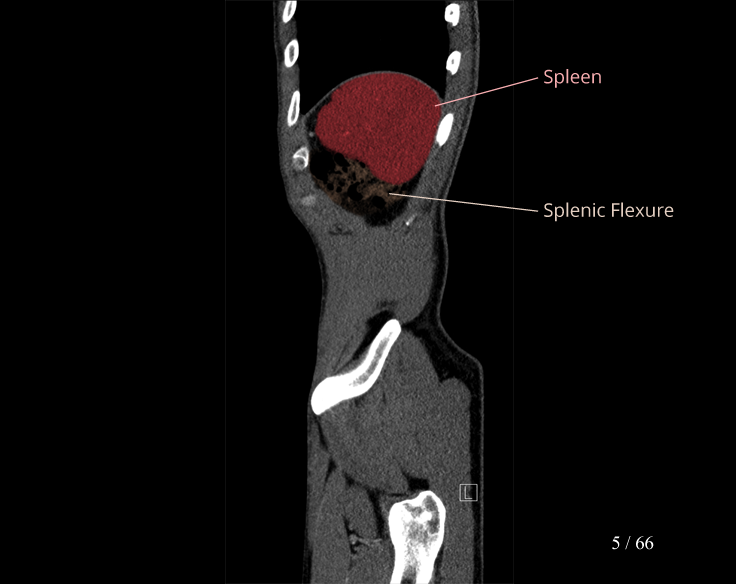

Body

Covers abdominal CT anatomy.